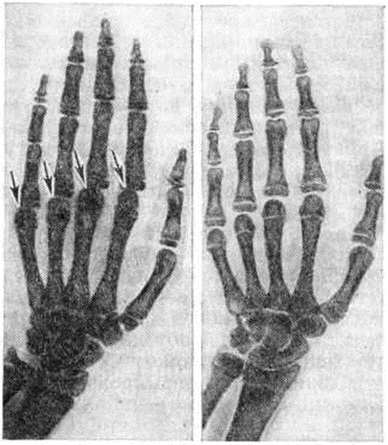

Клиническая картина. Болезнь начинается преимущественно в период роста организма, редко у лиц старше 25-летнего возраста. Процесс развивается, как правило, медленно, постепенно. Быстропрогрессирующие формы наблюдаются редко. Начальный период болезни протекает с непостоянными жалобами на ноющую боль в суставах и мышцах конечностей, в позвоночнике, спине, на скованность, хруст в дистальных суставах конечностей, парестезии, судороги пальцев и икроножных мышц. Деформации суставов и ограничения подвижности не обнаруживается. В развёрнутой клинический, картине заболевания принято выделять три степени тяжести. При I степени Кашина Бека болезнь жалобы становятся более постоянными, развивается умеренное утолщение проксимальных межфаланговых суставов II, III, IV пальцев кистей, движения в лучезапястных, голеностопных и иногда локтевых суставах слегка ограничены; в утренние часы или после физических нагрузки отмечаются боли в поражённых суставах. II степень характеризуется выраженностью и постоянством жалоб. При движениях в суставах выявляется хруст или треск. Объем движений в межфаланговых, лучезапястных, коленных, локтевых суставах значительно ограничен, суставы деформированы, утолщены. У части больных боль и хруст отмечаются также в плечевых, тазобедренных суставах и позвоночнике. Заметна атрофия мышц верхних и нижних конечностей, развиваются мышечные контрактуры. Появляется характерный симптом короткопалости (рисунок 5). Рост больных снижен (у мужчин в среднем 162,2 ± 0,5 сантиметров, у женщин 146,0 ± 0,5 сантиметров). При III степени все суставы конечностей деформированы и утолщены, движения в них резко ограничены. Характерен внешний вид больного: низкий рост (мужчины 160,2 ± 0,6 сантиметров; женщины 144,0 ± 0,5 сантиметров) преимущественно за счёт укорочения костей ног и в меньшей степени позвоночника, короткая шея, резко выраженная короткопалость («медвежья лапа»), genu valgum, genu varum, плоскостопие, компенсаторный лордоз поясничного отдела позвоночника, медленная, переваливающаяся («утиная») походка, у женщин часто узкий таз.

Рентгенологическое исследование позволяет уточнить локализацию и распространённость процесса в скелете, определить характер и степень выраженности изменений, динамически проследить за течением процесса. Для Кашина Бека болезнь характерна множественность и симметричность поражения. Вначале обычно поражаются суставные отделы основных и средних фаланг кистей, затем плюсневые и пястные кости (рисунок 6 и 7), кости лучезапястных, локтевых, голеностопных и коленных суставов; кости тазобедренного и плечевого суставов поражаются редко. Поэтому при массовых рентгенологическое исследованиях в первую очередь необходимо исследовать кисти и стопы. В начальной стадии заболевания патологический изменения локализуются в области ростковых зон костей. Зона предварительного обызвествления метафизов изгибается, утолщается, структура становится рыхлой, негомогенной, а поверхность, обращённая к эпифизу,— неровной и нечёткой. Метафизы бокаловидно расширяются, и в них погружаются эпифизы. Эпифизы деформированы, сплющены, увеличены в поперечнике (рисунок 6) и выступают в стороны в виде плоских чаш. Суставные поверхности костей выпрямлены и в субхондральных отделах склерозированы. Сроки появления ядер окостенения нарушены за счёт ускоренного созревания костной системы. Позвонки поражаются сравнительно редко. Кости мозгового черепа могут поражаться изолированно при нервно-висцеральной форме болезни: характерно наличие множественных лакунарно-кистозных просветлений в спонгиозном веществе (Б. Н. Ерофеев, А. В. Вощенко, 1977). Нередко наблюдается пародонтоз (смотри полный свод знаний) в виде краевых разрежений вдоль альвеолярных отростков челюстей. Суставные и межпозвоночные щели суживаются, но степень выраженности сужения зависит от характера изменений в кости и длительности заболевания. По мере прогрессирования заболевания происходит укорочение и искривление трубчатых костей. Характерно раннее синостозирование эпифизов с метафизами и преждевременное прекращение роста скелета. В дальнейшем развивается деформирующий артроз (смотри полный свод знаний) с образованием внутрисуставных тел и усилением рельефа костей у мест прикрепления связочно-сумочного аппарата.